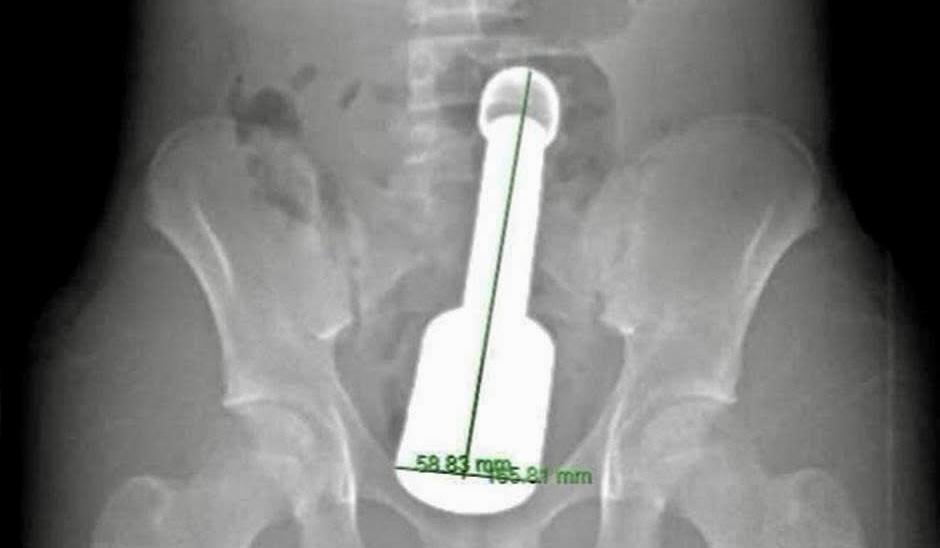

Hình ảnh chiếc chày kim loại dài 18 cm, đường kính 6 cm mắc kẹt trong hậu môn bệnh nhi

Sau hơn 45 phút, dị vật là chiếc chày kim loại dài 18 cm, đường kính 6 cm đã được lấy ra hoàn toàn qua đường hậu môn.

Chiếc chày không chỉ to (đường kính 6 cm, là giới hạn cực đại đối với cơ thắt hậu môn của một thiếu niên) mà còn rất nặng và tạo ra “hiệu ứng chân không” phía trên đỉnh dị vật, khiến nó bị hút chặt vào lòng ruột.